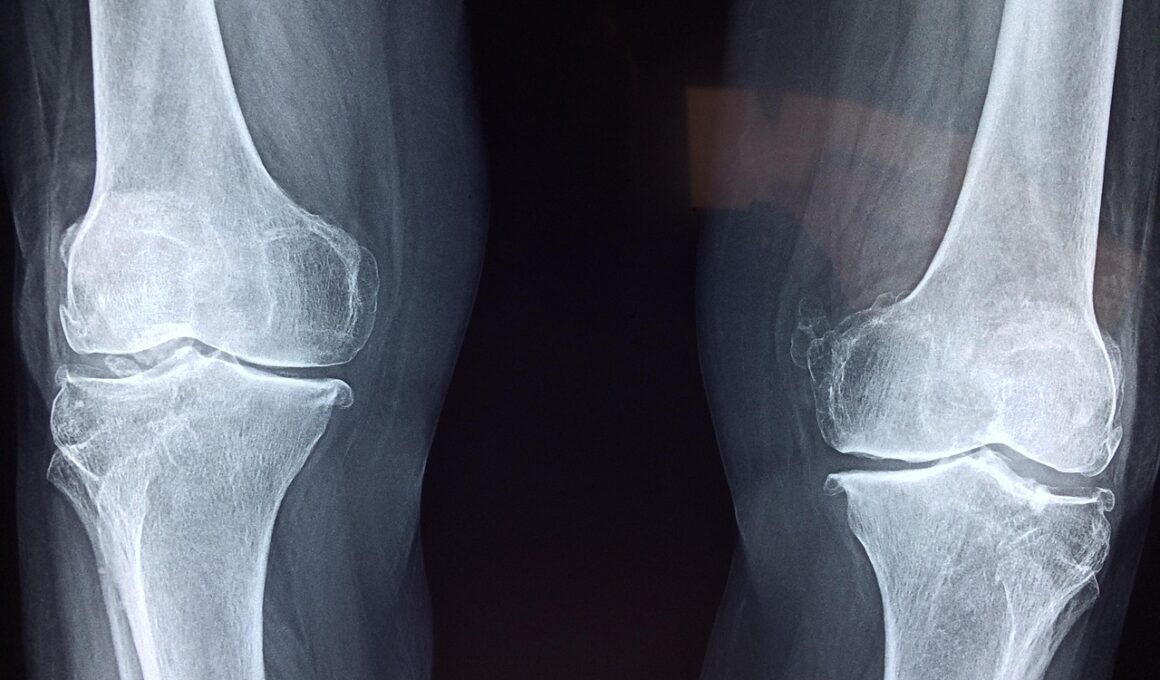

In addition to exercise, maintaining a healthy weight is crucial for protecting your joints. Excess weight can put significant strain on load-bearing joints, such as the knees and hips. A balanced diet rich in fruits, vegetables, lean proteins, and whole grains can assist in achieving and maintaining a healthy weight. Reducing the intake of processed foods high in sugar and saturated fats can also decrease inflammation, benefiting joint health. Regularly monitoring caloric intake may further help in managing weight effectively. Portion control may be essential in preventing overeating. Moreover, consider consulting a dietitian to craft a personalized nutrition plan suited to your needs. Engaging in mindful eating practices can promote a positive relationship with food, while also supporting your wellness goals. Aim to implement regular physical activity into your routine without overcommitting, ensuring sustainability. Simple changes like taking the stairs instead of the elevator can make a considerable difference over time. Prioritizing healthy habits in your lifestyle can lead to improved joint health and overall wellness, making activities more enjoyable and less painful long-term.